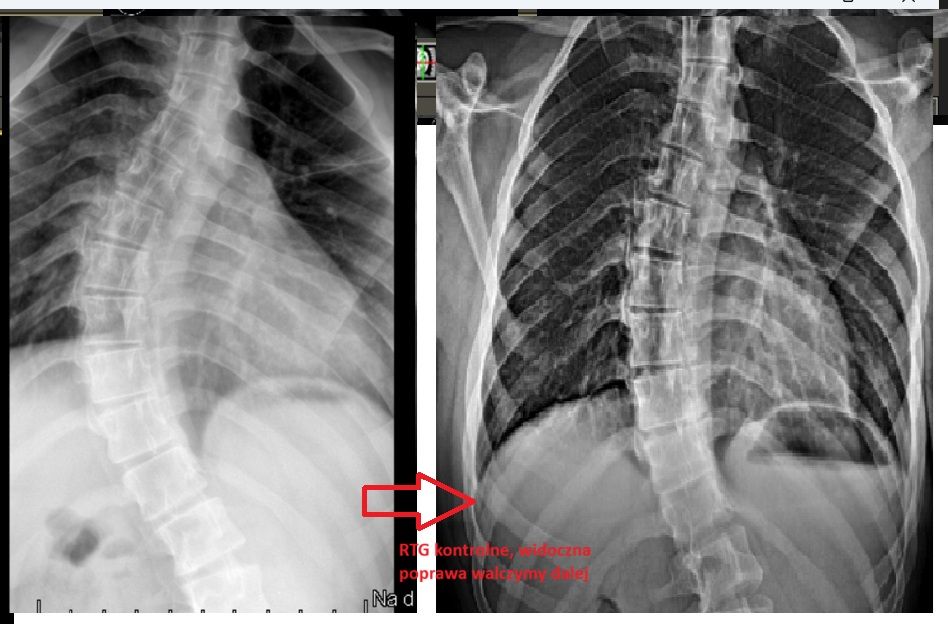

- Skolioza

Wizualna korekcja jest możliwa nawet i u starszych osób. Wszystko zależy od rodzaju i stopnia skoliozy. Odpowiednio dobrana terapia nie tylko poprawia komfort życia niwelując ból ale wpływa , na układ krążenia czy właśnie na wizualny aspekt postawy ciała.